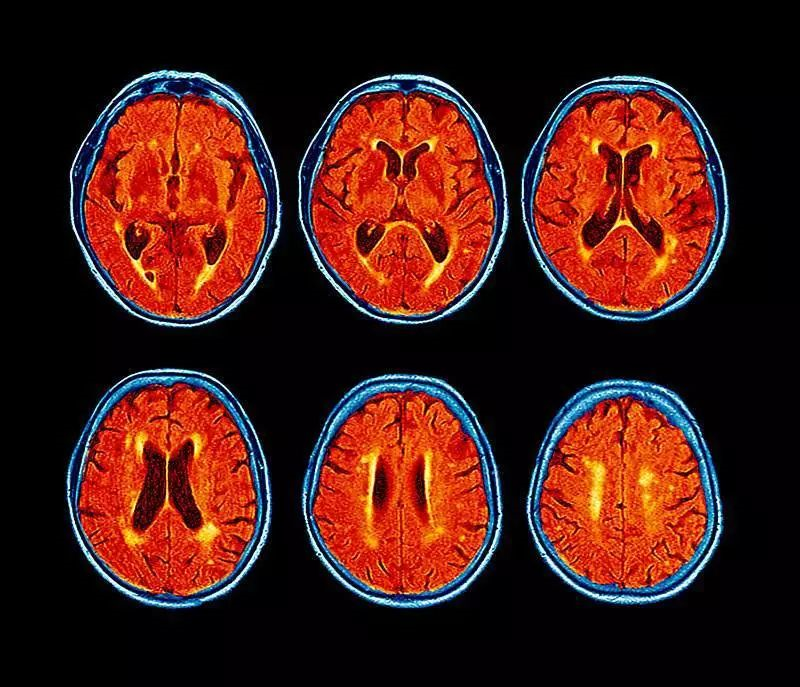

研究人员让参加研究的孕妇们在孕晚期时佩戴两天监测仪器,以此估测她们在长期内的环芳香烃暴露水平,等她们的子女满7至9岁时,需要接受学术测试和核磁共振扫描。

结果发现,环芳香烃暴露程度更高的儿童的大脑左半球的白质体积普遍较小。

白质是一种浅白色的脂肪状物质,是神经元的“绝缘体”,可帮助神经元通过电化学信号高效沟通。白质体积较小往往伴随更外化的行为、注意力不足过动症、以及较慢的信息处理速度,但这些研究结果也许不具有普适性,毕竟研究人员只考察了40名儿童,并且只关注了孕期内一段很短的时间。

2018年,研究人员又仔细分析了一遍这些研究结果。在分析了一份由351名儿童组成、且在人口统计学上很相似的样本后,发现那些环芳香烃暴露水平高、并且缺乏营养食物、住房、市政设施、以及衣物的儿童更容易出现注意力不足过动症的症状。